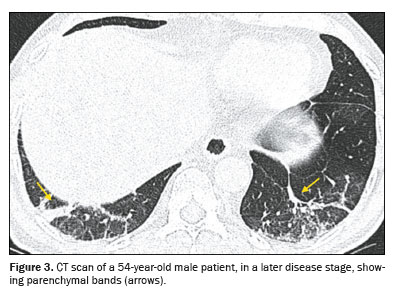

Ground-glass opacity (Figure 1) is characterized by increased lung density that does not obscure the internal vascular structures and should be differentiated from consolidation, in which the vessels are not visible. When accompanied by thickening of the interlobular septa, it forms what is known as the crazypaving pattern, which was not observed in our study sample. An air bronchogram (Figure 2) is defined as visible aerated bronchi within areas of consolidation or atelectasis. The interlobular septa, which delimit the secondary pulmonary lobule, are composed of connective tissue, pulmonary veins, and lymphatic vessels; the septa can present smooth, irregular, or nodular thickening in conditions such as edema, inflammation, fibrosis, and neoplasia. A parenchymal band (Figure 3) is an elongated linear opacity, commonly peripheral and accompanied by fibrosis or interstitial thickening, frequently in contact with the pleura, which can present thickening and retraction

(19).